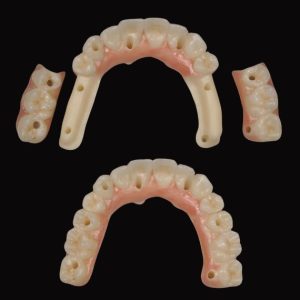

From A to Z Master Hands-On Course for No crestal bone loss